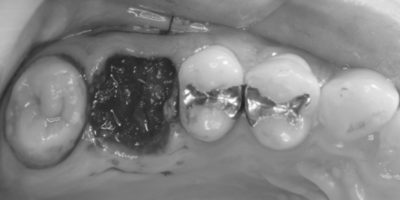

初診時口腔内写真

初診時パノラマX線写真と口腔内写真。

右上6に腫脹と排膿がみられた。